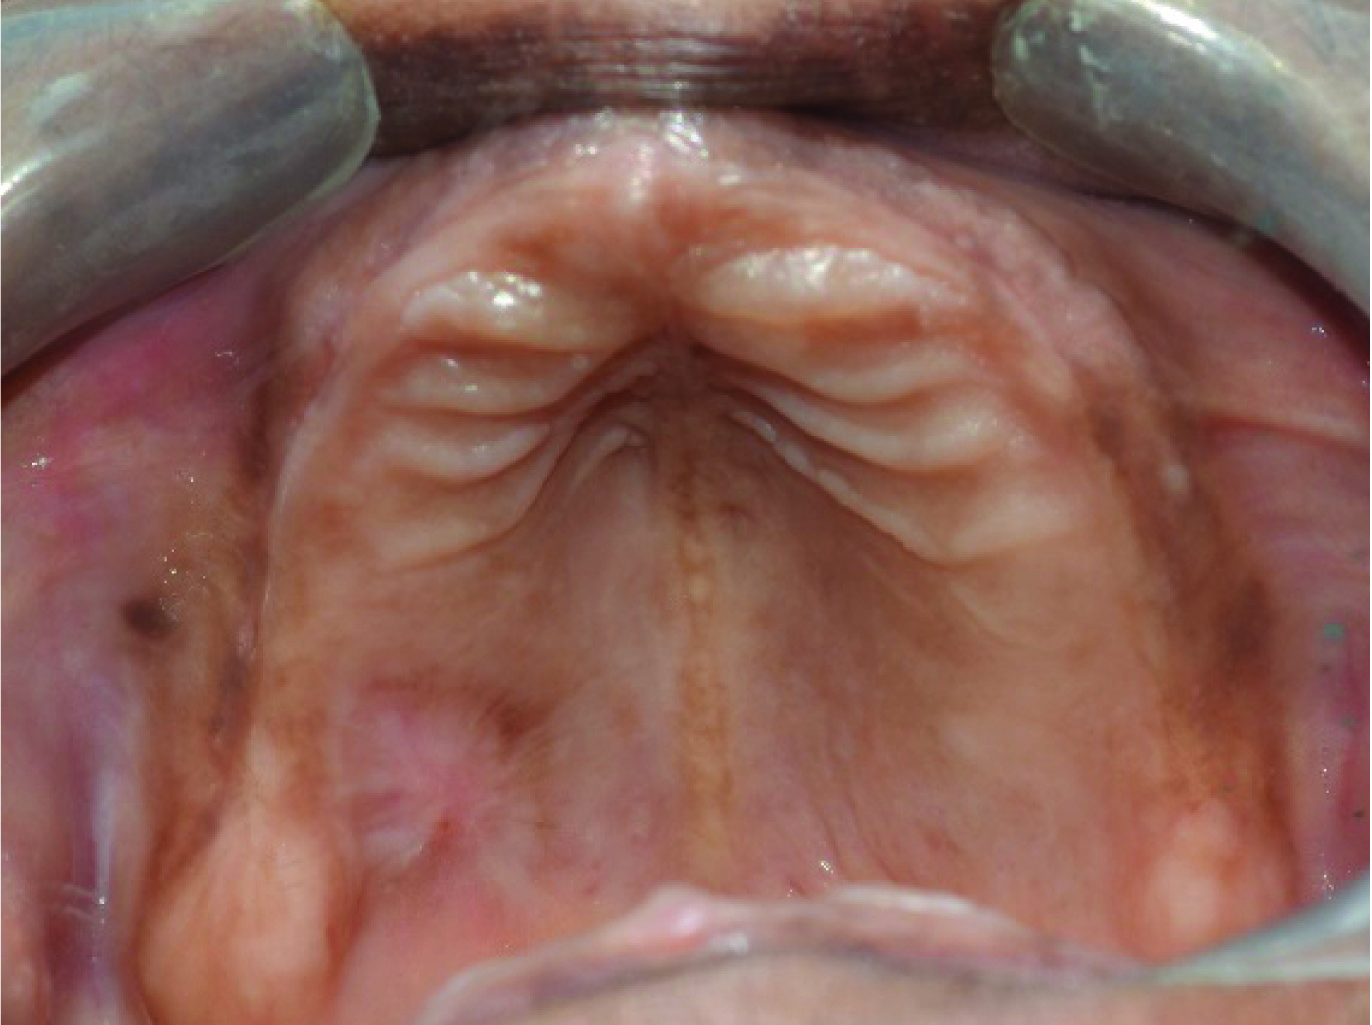

A 55-year-old Indian female reported to the Department of Oral and Maxillofacial Surgery, Faculty of Dental Sciences, Sri Ramachandra University in 2015 with a complaint of a swelling on the right side of the palate for the past one month [Table/Fig-1]. Patient revealed a medical history of Type one diabetes mellitus under control with oral hypoglycaemics (Tab Metformin 500 BID and Tab. Glyciphage BID) for past 10 years. On intraoral examination, patient was completely edentulous and was wearing complete denture. As there was swelling in the palate, she was unable to wear the denture. Clinical examination revealed a single well defined swelling of size 1.5cm x1.5cm in the right side of hard palate in relation to the missing 16, 17 region [Table/Fig-2]. The swelling appeared bluish in colour was soft, fluctuant and non-tender. No significant regional lymphadenopathy was present. Intra oral periapical radiograph revealed no evidence of bone loss in relation to 16 and 17. A provisional diagnosis of mucocele was considered with the clinical findings. Fine Needle Aspiration Cytology (FNAC) showed presence of red blood cells. This provoked us to consider lesions other than mucocele. Hence we planned for an open biopsy, as FNAC report advised us to correlate clinically. An excisional biopsy was performed under local anaesthesia using a 15 size BP blade and electro cautery due to the risk of bleeding. Haemostasis was achieved [Table/Fig-3]. A specimen of 10mm x 15mm was obtained [Table/Fig-4]. A periodontal dressing pack was placed on the maxillary complete denture to cover the defect and to reduce the oedema [Table/Fig-5]. Histopathological examination revealed thin squamous epithelium. The underlying connective tissue showed dense proliferation of adipose tissue along with dilated blood capillaries [Table/Fig-6]. There was no soft tissue infiltration or bony erosion and hence it was diagnosed to be a non-infiltrating type. A one week postoperative review showed healing defect in the palate [Table/Fig-7]. One month follow up showed satisfactory wound healing with minimal scarring. A three month postoperative follow up showed good wound healing with total disappearance of the lesion [Table/Fig-8]. A complete dental rehabilitation was performed for the patient [Table/Fig-9].

Intraoral Photograph show the lesion on the Right side of the Palate.